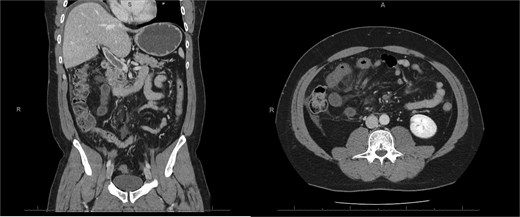

A 76-year-old female with a 3-day history of left upper abdominal pain, vomiting, and haematochezia. Her history included pulmonary embolism, multiple deep vein thromboses, with no ongoing anticoagulation, and an open partial colectomy for complicated diverticulitis a decade earlier. On admission, she was afebrile but tachycardic and showed localized tenderness in the left hypochondrium. Laboratory revealed leucocytosis with a white blood cell count (WBC) of 12 G/L, elevated C-reactive protein (CRP) of 46 mg/L, and hyperlactatemia of 2.6 mmol/l. Enhanced computed tomography (E-CT) revealed jejunal venous ischemia in the left upper quadrant, secondary to extensive porto-mesenteric thrombosis with reduced bowel wall enhancement, distention, and free intraperitoneal fluid (Fig. 1). She was managed conservatively with unfractionated heparin (UFH) with a bolus of 5000 U/l followed by 30 000 U/l/24 h (target INR 0.35–0.7), Piperacillin-Tazobactam, and bowel rest. After 48 h of monitoring in the intensive care unit (ICU), she exhibited marked biological and clinical improvement. E-CT on the third day showed restored bowel wall enhancement and stable porto-mesenteric thrombosis (Fig. 2). She was discharged on therapeutic low molecular weight heparin (LMWH) with enoxaparin sodium 120 mg every 12 h. At the 3-month follow-up, E-CT revealed near-complete thrombus resolution, without intestinal sequelae (Fig. 3).

Three-month E-CT of the first patient showing nearly complete thrombosis resolution, with no signs of intestinal distress.